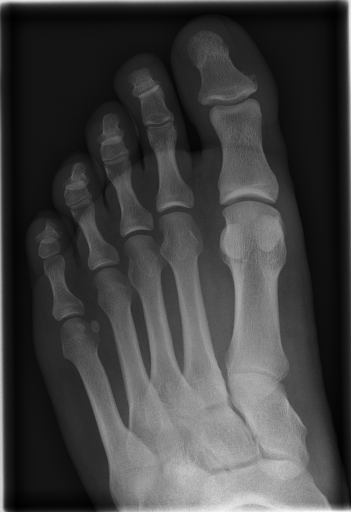

In this series of experiments, we randomly selected three categories from IRMA dataset (namely, breast, foot and lung), and for each category we choose 5 random images from that class (Figures 5, 6 and 7 show these images). When we find “4 out of 180” (4/180) and “8 out of 180” (8/180) projections via micro-DE (tasks that cannot be performed via brute-force), then the question is what can we say about the reconstruction error, in terms of correlation between original and reconstructed images, when we compare evolutionary approximation with the case that we can manage via exhaustive search, namely “4 out of 16” (4/16)? Can micro-DE reach at least the same correlation (similarity) as the brute-force case in lower dimensions? If yes, we may have more confidence in using micro-DE in practice where we cannot apply brute force for benchmarking or direct use, especially for higher dimensions (i.e., the number of projections).

| image | BF (4/16) | MDE (4/180) | MDE (8/180) | |||

|---|---|---|---|---|---|---|

| f1 | [34,67,112,157] | 0.79 | [30,80,110,150] | 0.80 | [80,160,30,130,30,100,140,60] | 0.85 |

| f2 | [79,101,135,169] | 0.73 | [80,110,140,170] | 0.73 | [70,20,160,0,120,80,130,100] | 0.80 |

| f3 | [11,56,112,158] | 0.64 | [20,60,100,170] | 0.65 | [40,130,160,70,10,170,110,60] | 0.70 |

| f4 | [11,79,101,169] | 0.77 | [0,30,80,100] | 0.77 | [20,180,50,60,80,110,170,120] | 0.84 |

| f5 | [22,67,112,157] | 0.85 | [80,30,120,160] | 0.86 | [120,60,80,10,150,100,170,40] | 0.89 |